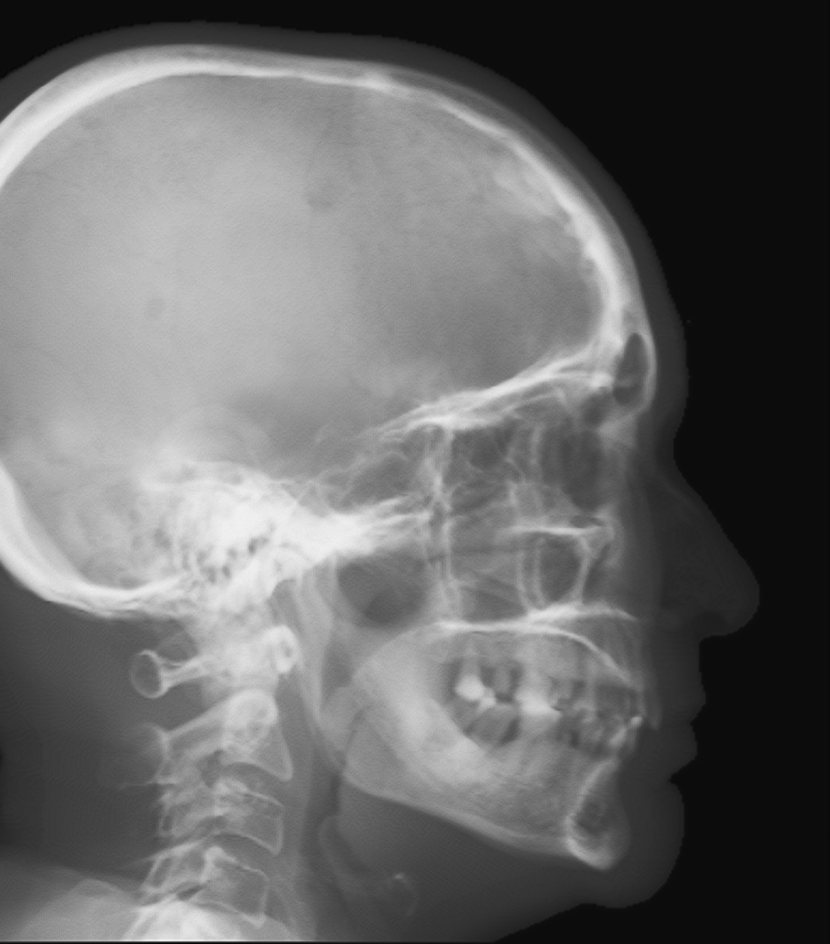

Refer to caption

(a) Real cephalogram

(b) Synthetic cephalogram

(c) Plot of samples and sigmoid curves

Fig. 2: Image contrast difference between real conventional cephalograms and RayCast synthetic cephalograms: (a) a real cephalogram example; (b) a RayCast synthetic cephalogram example; (c) the plot of samples between RayCast synthetic cephalograms and real cephalograms with an original sigmoid curve (red) and our proposed modified sigmoid curve (blue).

In Fig. 2, one real conventional cephalogram example and one example of 𝒈𝒈\boldsymbol{g} are displayed, where evident image contrast difference between these two images is observed. It is because the X-ray films used in conventional cephalograms have the special nonlinear optical property that the characteristic curve between optical density and logarithmized X-ray exposure has a sigmoid-like shape [42]. According to the Lambert-Beer law, the logarithmized X-ray exposure is equivalent to the attenuation integral. It indicates that the intensity relation between the desired cephalogram and the attenuation integral image 𝒈𝒈\boldsymbol{g} should also exhibit a sigmoid-like curve. Therefore, to make the image contrast of synthetic cephalograms similar to conventional cephalograms, a sigmoid intensity transform is necessary.